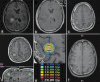

Results: With respect to newly diagnosed HGG, there is strong evidence that addition of an SRS boost prior to standard XRT provides no survival benefit. However, recent retrospective evidence suggests a possible survival benefit when SRS is performed after XRT. With respect to recurrent HGG, there is suggestion that SRS may confer a survival benefit but with potentially higher complication rates. Newer studies are investigating the combination of SRS with targeted molecular agents. Controlled prospective clinical trials using advanced imaging techniques are necessary for a complete assessment.